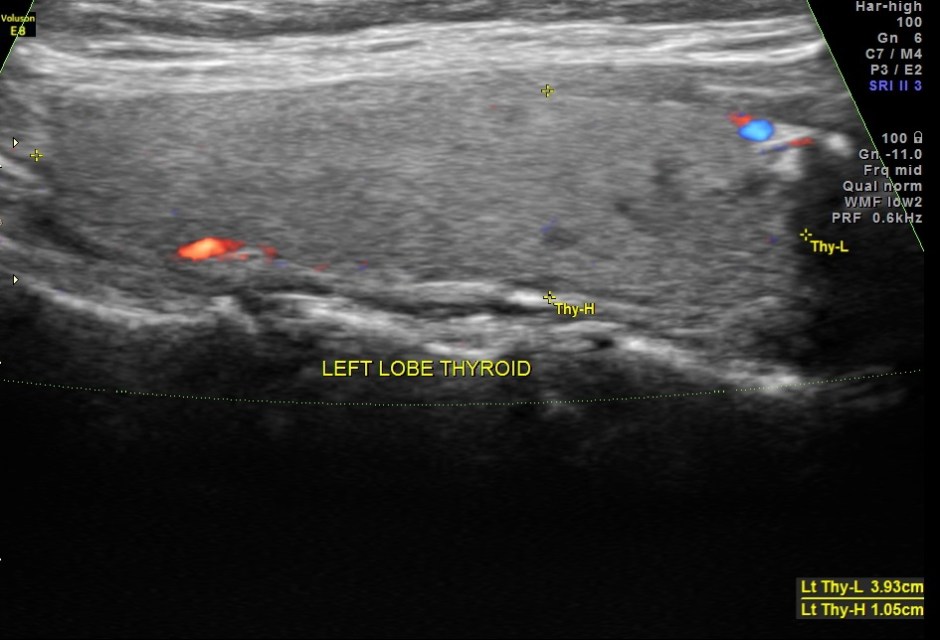

The left lobe of the thyroid and the isthmus appeared normal.